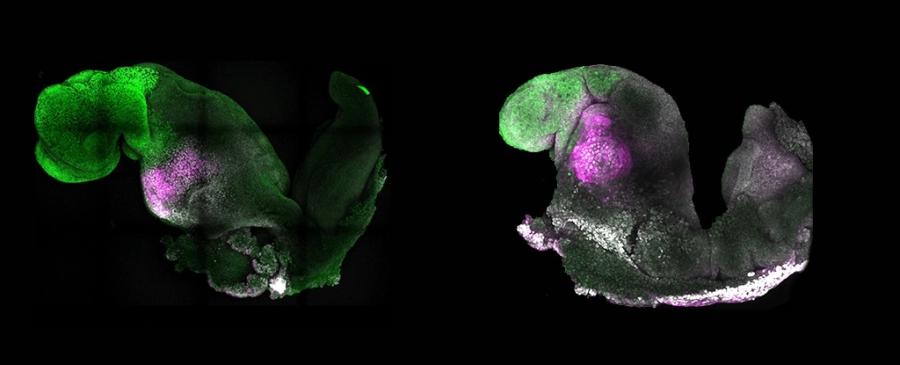

Учени създадоха синтетичен ембрион на мишка без участието на сперма и яйцеклетка, който започва формирането на органи, включително мозък и биещо сърце. Резултатите от изследването дават надежда на много семейства, които не могат да имат биологични деца. Те са плод на 10-годишни опити и са публикувани в сп. Nature от Магдалена Зерницка-Гьоц от Калифорнийския технологичен институт и нейни колеги.

Синтетичните ембриони са получени чрез комбинирането на три вида стволови миши клетки. В лабораторни условия учените изолирали трите вида стволови клетки от ембриони и ги култивирали в контейнери, след което наблюдавали ден след ден как групи от клетки започват да формират все по-сложни структури, включително подобна на сърце и на глава.